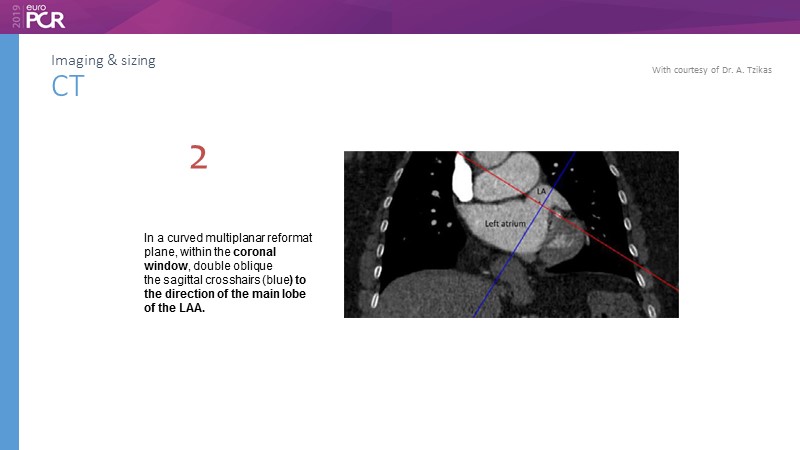

Pre-procedure planning

Previous Next